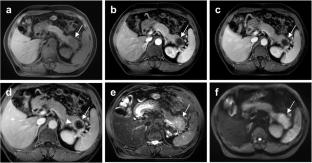

A total of 308 surgically confirmed PDAC patients (median age, 67 years [IQR, 59, 72]; 183 male and 125 female) with genetic testing data were included, of which 258 had KRAS-mutated PDAC and 50 had non-KRAS-mutated PDAC. KRAS-mutated PDAC demonstrated distinct clinicopathological characteristics, including higher rates of diabetes (OR, 2.450, 95% CI, 1.151–5.212, P = 0.020), pathological peripheral nerve infiltration (OR, 2.296, 95% CI, 1.083–4.867, P = 0.030), and pN stage (OR, 2.006, 95% CI, 1.012–3.976, P = 0.046). The 1-, 3-, 5-year OS rate was worse for KRAS-mutated PDAC (89.9%, 45.4%, 23.2% vs. 95.1%, 60.4% 60.4%, P = 0.045). Rim enhancement (OR = 2.039, 95% CI: 1.053, 3.951, P = 0.035) and larger tumor size (OR = 3.286, 95% CI: 1.523, 7.089, P = 0.002) were identified as distinctive MRI features for KRAS-mutated PDAC.

KRAS-mutated PDAC presents unique clinical and pathological features and is associated with poorer prognosis. Rim enhancement and larger tumor size on MRI were identified as features associated with KRAS-mutated PDAC.